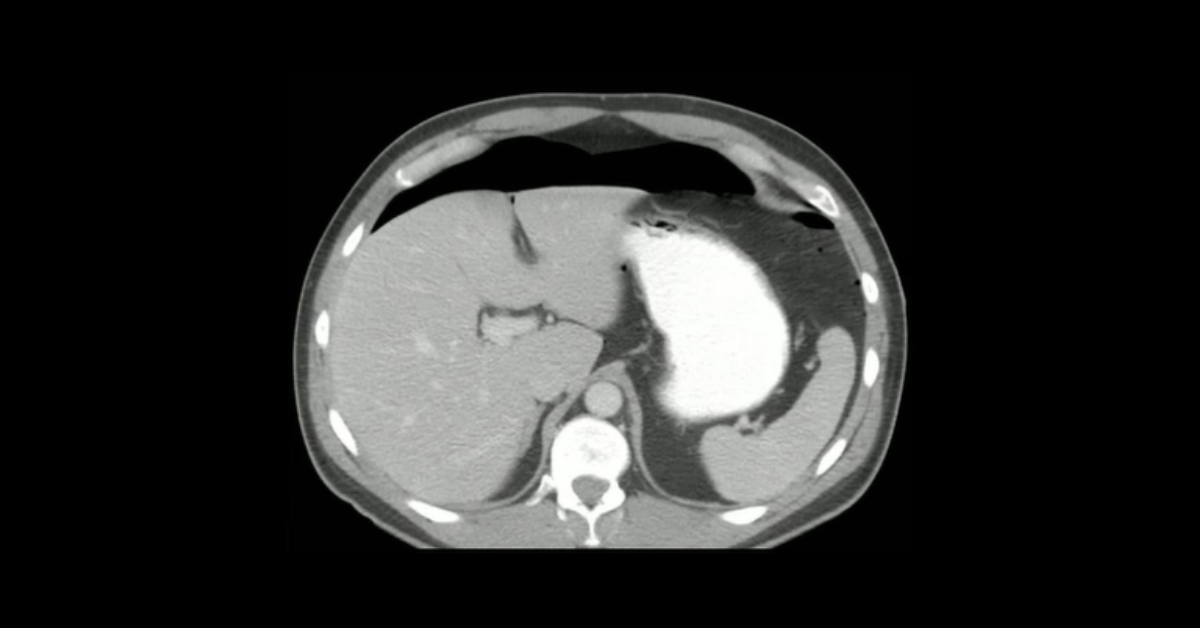

Presented by Vincent Mellnick, MD at Practical Radiology 2025. The upper gastrointestinal tract can be oft-overlooked site of disease in the emergency department patient, but is frequently be the site of pathology, including inflammation/infection, ischemia, obstruction, perforation, and hemorrhage. This talk will discuss common (and some uncommon) conditions causing these presentations in the esophagus, stomach, and duodenum, with emphasis on CT findings.